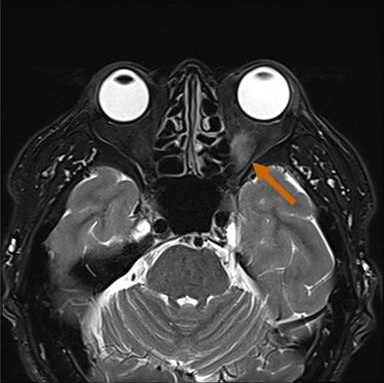

長崎甲状腺クリニック(大阪)では、メルカゾール(5mg)0.5T/日投与により数年間、甲状腺機能正常を維持している安定したバセドウ病患者にいきなり遅延型バセドウ病眼症が起こりました。そのMRI画像がこれです。

同じく、甲状腺亜全摘出20年後発症した遅延型バセドウ病眼症もありました。

バセドウ病眼症(甲状腺眼症)診断目的のため行った眼窩MRI検査で、偶然、下垂体腺腫が見つかる場合があります。下は、左眼バセドウ病眼症(眼筋炎)、下垂体腺腫、上顎洞炎・鼻茸が合わせて見つかったケースです。下垂体腺腫が視神経交叉を押し上げているため、病態は複雑になります。